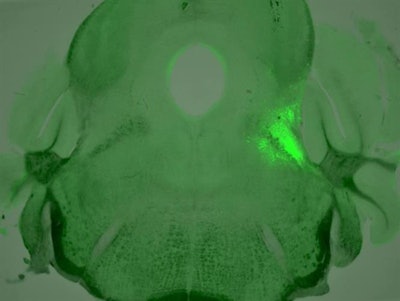

We labeled the neurons projecting to the breathing and pain centers with multicolored fluorescent proteins. In doing this, we were able to identify two subsets of neurons that express µ-opioid receptors. These neurons were arranged in a core-shell shape, where one subset of neurons are wrapped around the other subset. The outer shell neurons regulate breathing by sending their axons -- the long part of the neuron that transmits electrical signals -- to the part of the brainstem that controls breathing. The inner core neurons, on the other hand, mediate pain and anxiety by sending their axons to the brain's pain and emotion center, the amygdala.